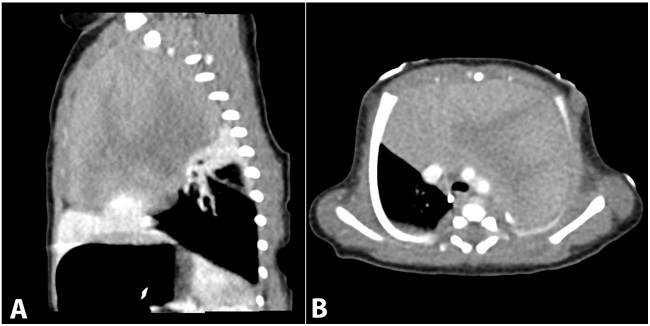

The patient is a male infant born at 39-week gestation with an unremarkable prenatal history via uncomplicated vaginal delivery. Normal anatomy was reported at a 23-week ultrasound examination. At birth, APGAR scores were 6/7/7 when the patient was diagnosed with transient tachypnea of the newborn. A chest X-Ray revealed a large mediastinal mass. Computed tomography revealed a 9x5x5 cm solid, heterogeneous mass in the anterior mediastinum, which displaced the heart, great vessels and lungs without invasion or narrowing of the airway (Figure 1). At this time the differential diagnosis included: thymic hyperplasia, thymoma, lymphoblastic lymphoma, germ cell tumor, teratoma and hiatal hernia.